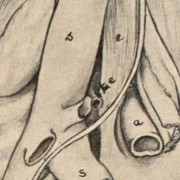

Lilly Ebstein Lowenstein (1897-1966) led a life between science and art, drawing and taking photographs in the fields of Medicine and Zoology. In her work, Lilly combined her technical knowledge of photography and drawing, the study of the sciences and a remarkable talent for aesthetics. She was born in Germany and studied at the Lette-Verein School in Berlin from 1911 to 1914. In 1925, she immigrated with her husband and two children to São Paulo. In 1926, she became an illustrator and photomicrographer at the Illustration and Photography Department at the School of Medicine (USP, as of 1934), which she headed for thirty years after 1932. Lilly collaborated at Instituto Biológico de Defesa Agrícola e Animal (the Biological Institute for the Defense of Agriculture and Animals), from 1930 to 1935, namely in the Avian Pathology Department. A life with art dedicated to the research and dissemination of science.